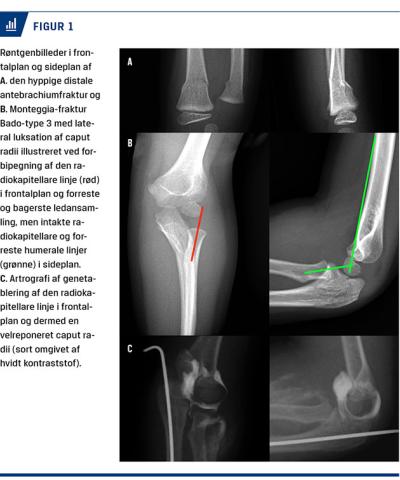

En fireårig ellers rask pige blev indbragt til skadestuen pga. hævelse og smerter fra venstre håndled og albue efter et fald fra en gynge tidligere på dagen. Man konstaterede et håndledsbrud og en olecranonfraktur

med normale neurovaskulære forhold (Figur 1A + B).

Ved røntgenkonference næste dag blev det konstateret, at den radiokapitellare linje pegede lateralt forbi capitulum humeri, hvilket er foreneligt med en lateral luksation af caput radii. To dage efter skaden blev patientens Monteggia-frakturluksation (Bado-type 3) og ipsilaterale distale antebrachiumfraktur reponeret og førstnævnte ligeledes k-trådsfikseret (Figur 1C). En artrografi med jodholdigt kontraststof viste, at caput radii var reponeret og stabil i hele albueleddets bevægeomfang – særligt i fuld pronation.

Den radiokapitellare linje bør ramme capitulum humeri centralt uanset røntgenprojektion. Hvis den rammer forbi i en enkelt projektion, som hos patienten i

sygehistorien, bør man have mistanke om en caput

radii-luksation [3, 4]. I tvivlstilfælde kan en dynamisk artrografi i generel anæstesi være en stor hjælp. Luksation af caput radii ved Monteggia-frakturluksationer vil ofte være tydeligst i fuld pronation. Nøglen til en god prognose ved Monteggia-frakturluksationer er tidlig diagnose og behandling, som genskaber de anatomiske forhold omkring albuen.